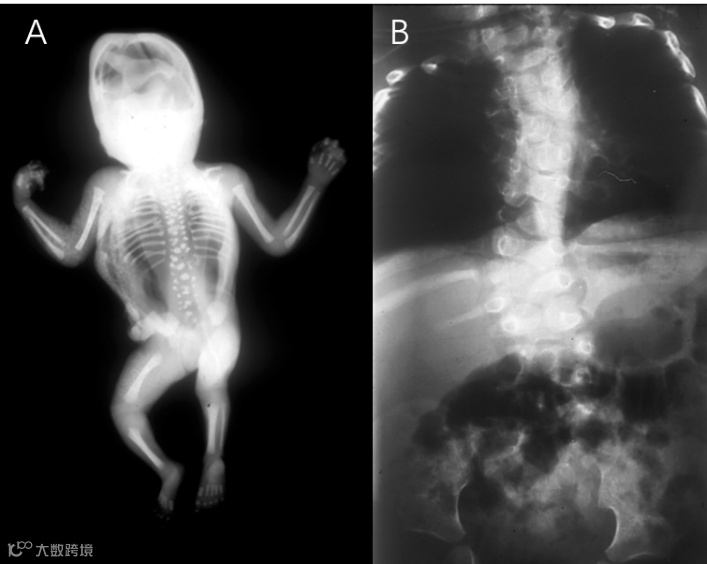

SCDO1型患儿在生命早期(胎儿或幼儿时期)每个椎体为圆形或卵形,边界光滑,这种现象被称为“卵石滩特征”。随着儿童期中期至晚期骨化的进行,卵石滩变为多个不规则形状的椎体和半椎骨。

SCDO2型患者所有椎骨节段均显示出一些形态和形状的异常;肋骨在肋骨交界处完全融合,从而产生“蟹状”特征;脊柱和躯干的缩短会严重影响儿童早期的呼吸功能。

SCDO3型患者脊椎的缩短比SCDO1和SCDO2型更严重,所有椎体均显示出更严重的畸形。

SCDO3型

SCDO4型患者的所有椎体畸形程度都异常严重。与SCDO1相比,椎弓根相对突出(“蹦床”特征)。

SCDO4型

SCDO5型患者临床症状出现更早,以下半段脊柱的半椎体和蝴蝶椎为典型特征。